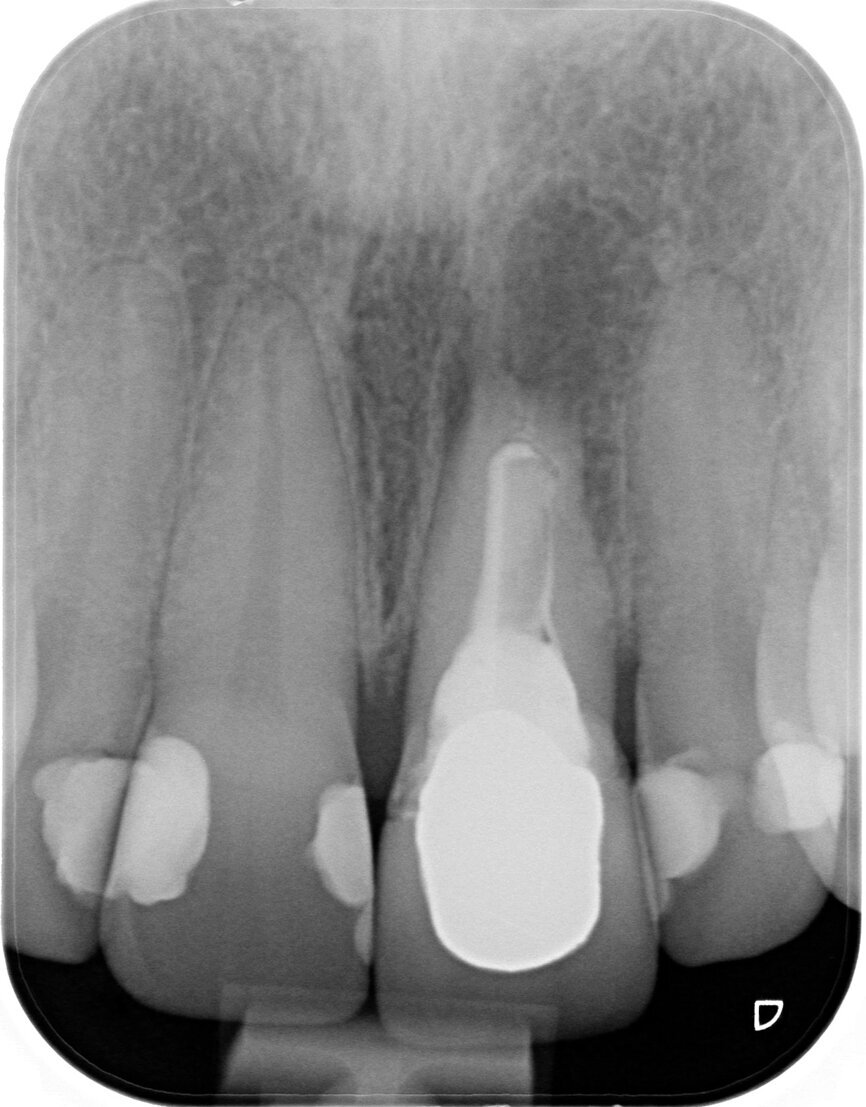

A 40-year-old female patient presented to our dental surgery with an irreparable tooth #21 (Fig. 1). The periapical radiograph revealed an approximately 7 mm periapical translucency with widening of the periodontal ligament in the upper third of the root (Fig. 2). Owing to the clinical conditions (high smile line and good oral hygiene), we decided to use a two-piece ceramic implant, ZERAMEX XT (Dentalpoint).

Fig. 2: Initial radiographic examination.

A provisional crown made of GRADIA (GC), a microceramic composite, was fabricated to achieve optimum contouring of the marginal gingiva in the highly aesthetic zone. A PEEK abutment (ZERAMEX Provisional RB; 180-day maximum period of wear), with a screw (maximum torque of 15 Ncm), acted as the base for the long-term temporary restoration (Figs. 8a & b). After eight weeks and adjusting the long-term temporary restoration in the basal area twice to optimise the emergence profile, the definitive zirconia crown (Ceramill substructure, Amann Girrbach; Creation veneer) was fixed to the customised abutment made of alumina-toughened zirconia (Figs. 9 & 10). After exact positioning (checked by probing or by taking a radiograph) the abutment is firmly fixed by utilising the VICARBO screw which is part of the ZERAMEX system. This unique screw made of carbon fibre-reinforced high-performance polymer is tightened to a torque of 25 Ncm. The final result is shown in Figure 11. The examinations after six and 12 months found no irritation of the soft tissue, and the BOI test was negative. The pink aesthetic score according to Fürhauser was 12 out of a maximum of 14 points (Figs. 12a & b).15 The process of peri-implant bone remodelling was of particular interest. Examinations were performed with periapical radiographs (right angle technique) and DBSWIN software (Dürr Dental).

Bone resorption was detected six months after exposure (mesial bone: 0.6 mm; distal bone: 0.4 mm), and a gain of bone was observed 12 months after exposure (mesial bone: 0.0 mm; distal bone: 0.3 mm; Figs. 13a–c). In accordance with the findings in the relevant literature, bone resorption in our patient was the greatest in the first six months.16 However, the literature findings are in reference to one-piece ceramic implants, in contrast to the two-piece implant system used in this case. This phenomenon of bone resorption is a relatively rare occurrence in implantology and should be confirmed by evidence-based long-term studies before a definitive conclusion can be drawn. Evaluations are in progress.